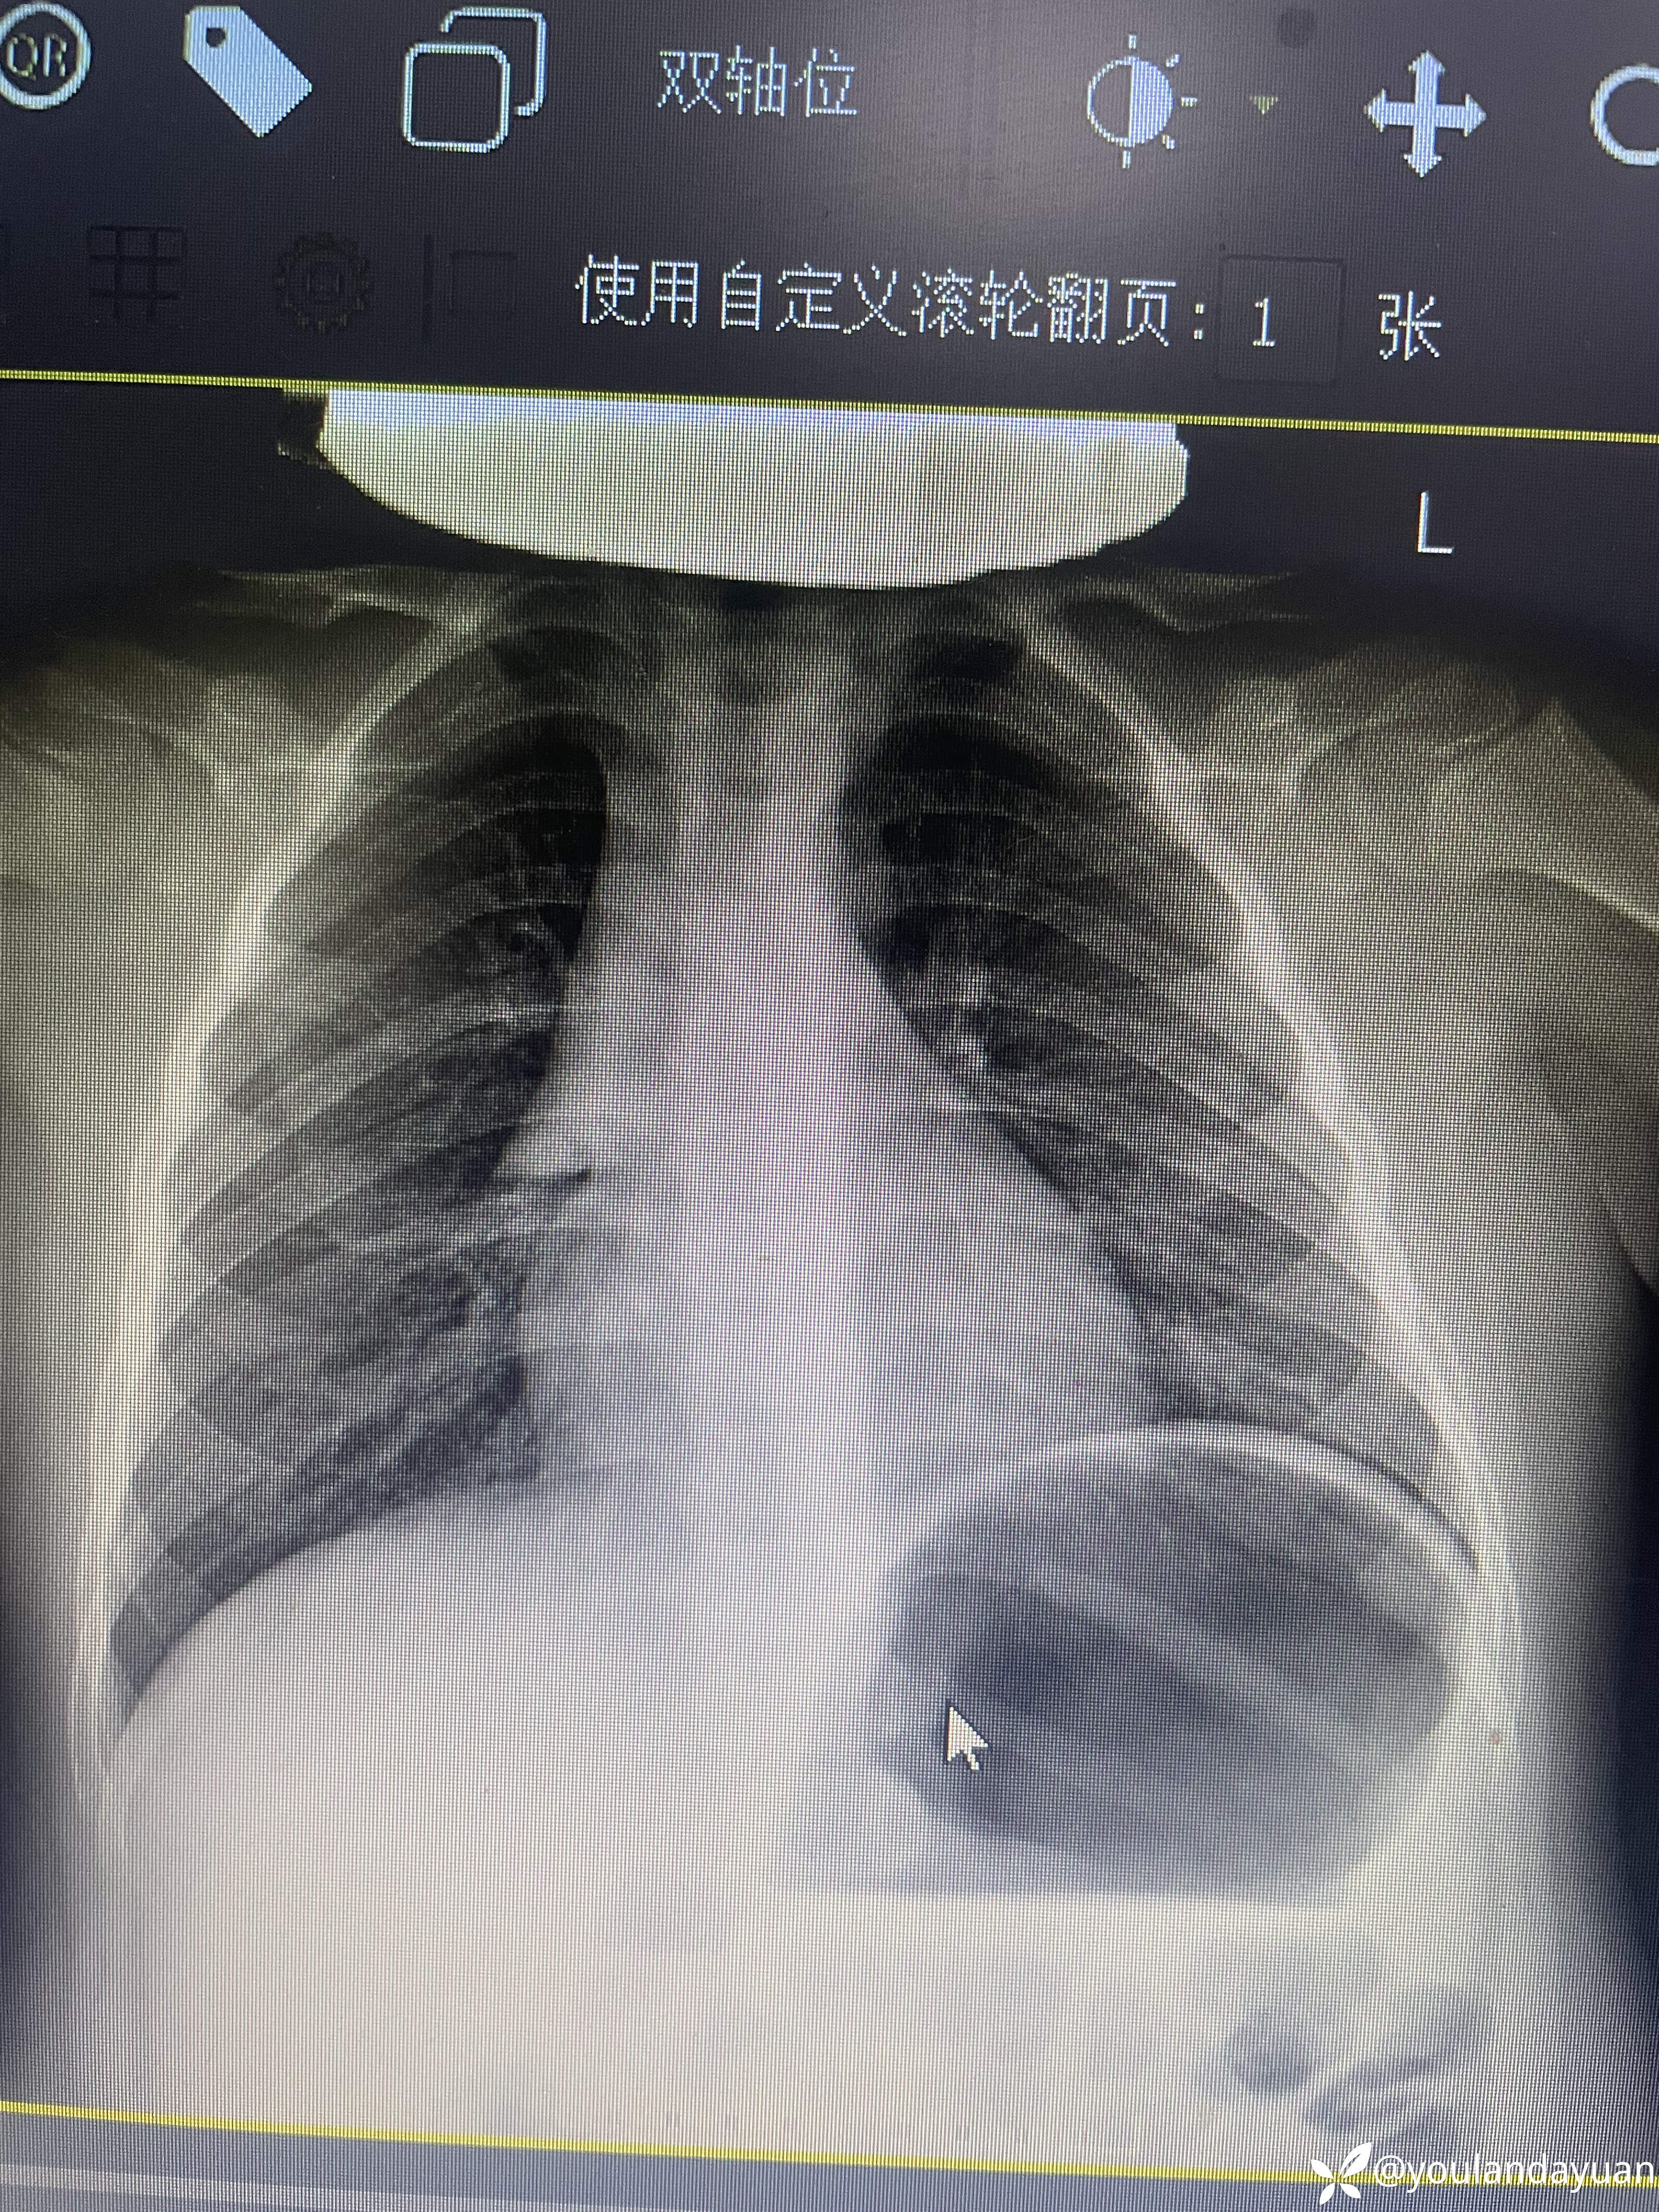

6岁儿童咳嗽50天,咳血两次

文侠 推荐患儿系50天前无明显诱因出现咳嗽,有轻度鼻炎病史,最初居家观察,20天前就诊我科,胸前提示支气管炎,肺炎支原体IGM阳性,考虑支原体感染,支气管炎,

并给予,“头孢泊肟,阿奇,氯雷他定”5天,环酯红霉素5天,咳嗽明显减轻。停药5天后出现咳血两次。

今日复查胸片